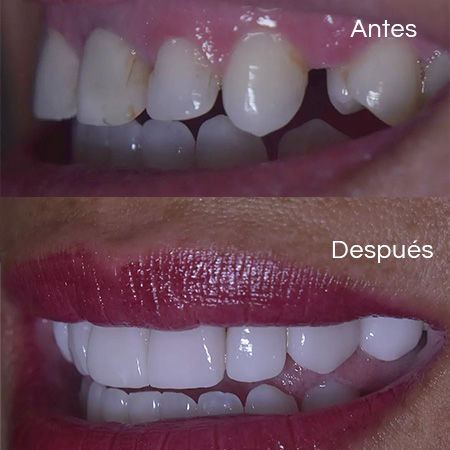

Before and After Gallery